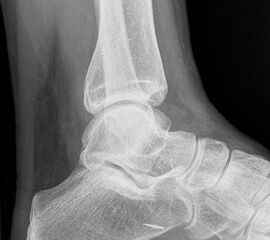

Sprunggelenk Mortise Aufnahme ohne Belastung (Mortise-View)

Positionierung:

• Zur Abbildung der Sprunggelenkgabel wird der Fuß 20° innenrotiert, um eine exakte ap-Abbildung der Malleolengabel zu erreichen.

• In dieser Aufnahme wird der mediale und laterale Gelenkspalt des Talus mit identischer Breite abgebildet.

• Innen- und Außenknöchel befinden sich in gleicher Distanz zum Röntgenfilm.

• Zentralstrahl wird mittig auf den Gelenkspalt am oberen Sprunggelenk zentriert.

Kennzeichen des Röntgenbildes:

• Darstellung des Talusdoms ohne Überlagerung.

• Das Sprunggelenk befindet sich dabei in 90° Stellung, um eine Überlappung des Kalkaneus mit der distalen Fibula zu vermeiden.

• Der Weichteilmantel ist erkennbar.

Besondere Bemerkungen zum Beispielbild:

• Die Innenknöchelfraktur ist deutlich besser nachvollziehbar als bei der ap Aufnahme (siehe vorheriges Bild).

• Keine Stufe im Gelenk.

• Die Wachstumsfugen sind noch erkennbar, im Wesentlichen aber geschlossen.